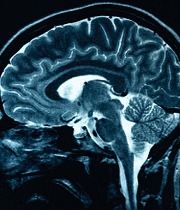

Muchas áreas del cerebro lidian con las tareas sociales pero los científicos de la Universidad Duke han identificado una que actúa específicamente cuando se encuentra un contrincante y se pondera engañarlo, según un artículo que publica la revista Science.

ImagenLas interacciones sociales causan que el cerebro opere bajo reglas diferentes y pueden influir en la forma en que se toman las decisiones, señala el artículo.

Los participantes jugaron sus partidas conectados a un aparato de imagen funcional por resonancia magnética (MRIf) y, mediante algoritmos por computador, los investigadores escanearon 55 regiones del cerebro y pudieron discernir el volumen de información procesado por cada área del cerebro.

Así encontraron que una sola región cerebral, la conjunción temporal parietal (CTP), se ocupa de la información específica acerca de las decisiones tomadas contra otro humano.

La CTP es un área del cerebro donde se encuentran los lóbulos temporal y parietal en el extremo posterior de la cisuria de Silvio o surco lateral, y que los científicos han determinado que desempeña un papel crucial en los procesos de distinción del yo y los otros.